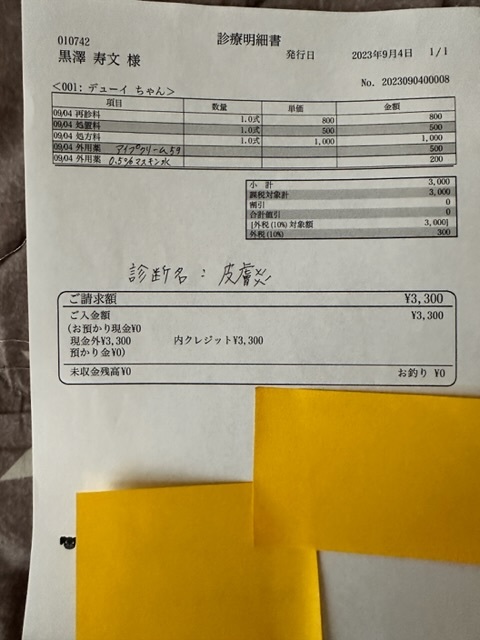

実際にかかった治療費

★

★

★

★

▶︎ 4. 掲載している資料について

ページ上に掲載している診断書や診療明細書などの資料は全て動物病院から掲載の許諾を得ております。